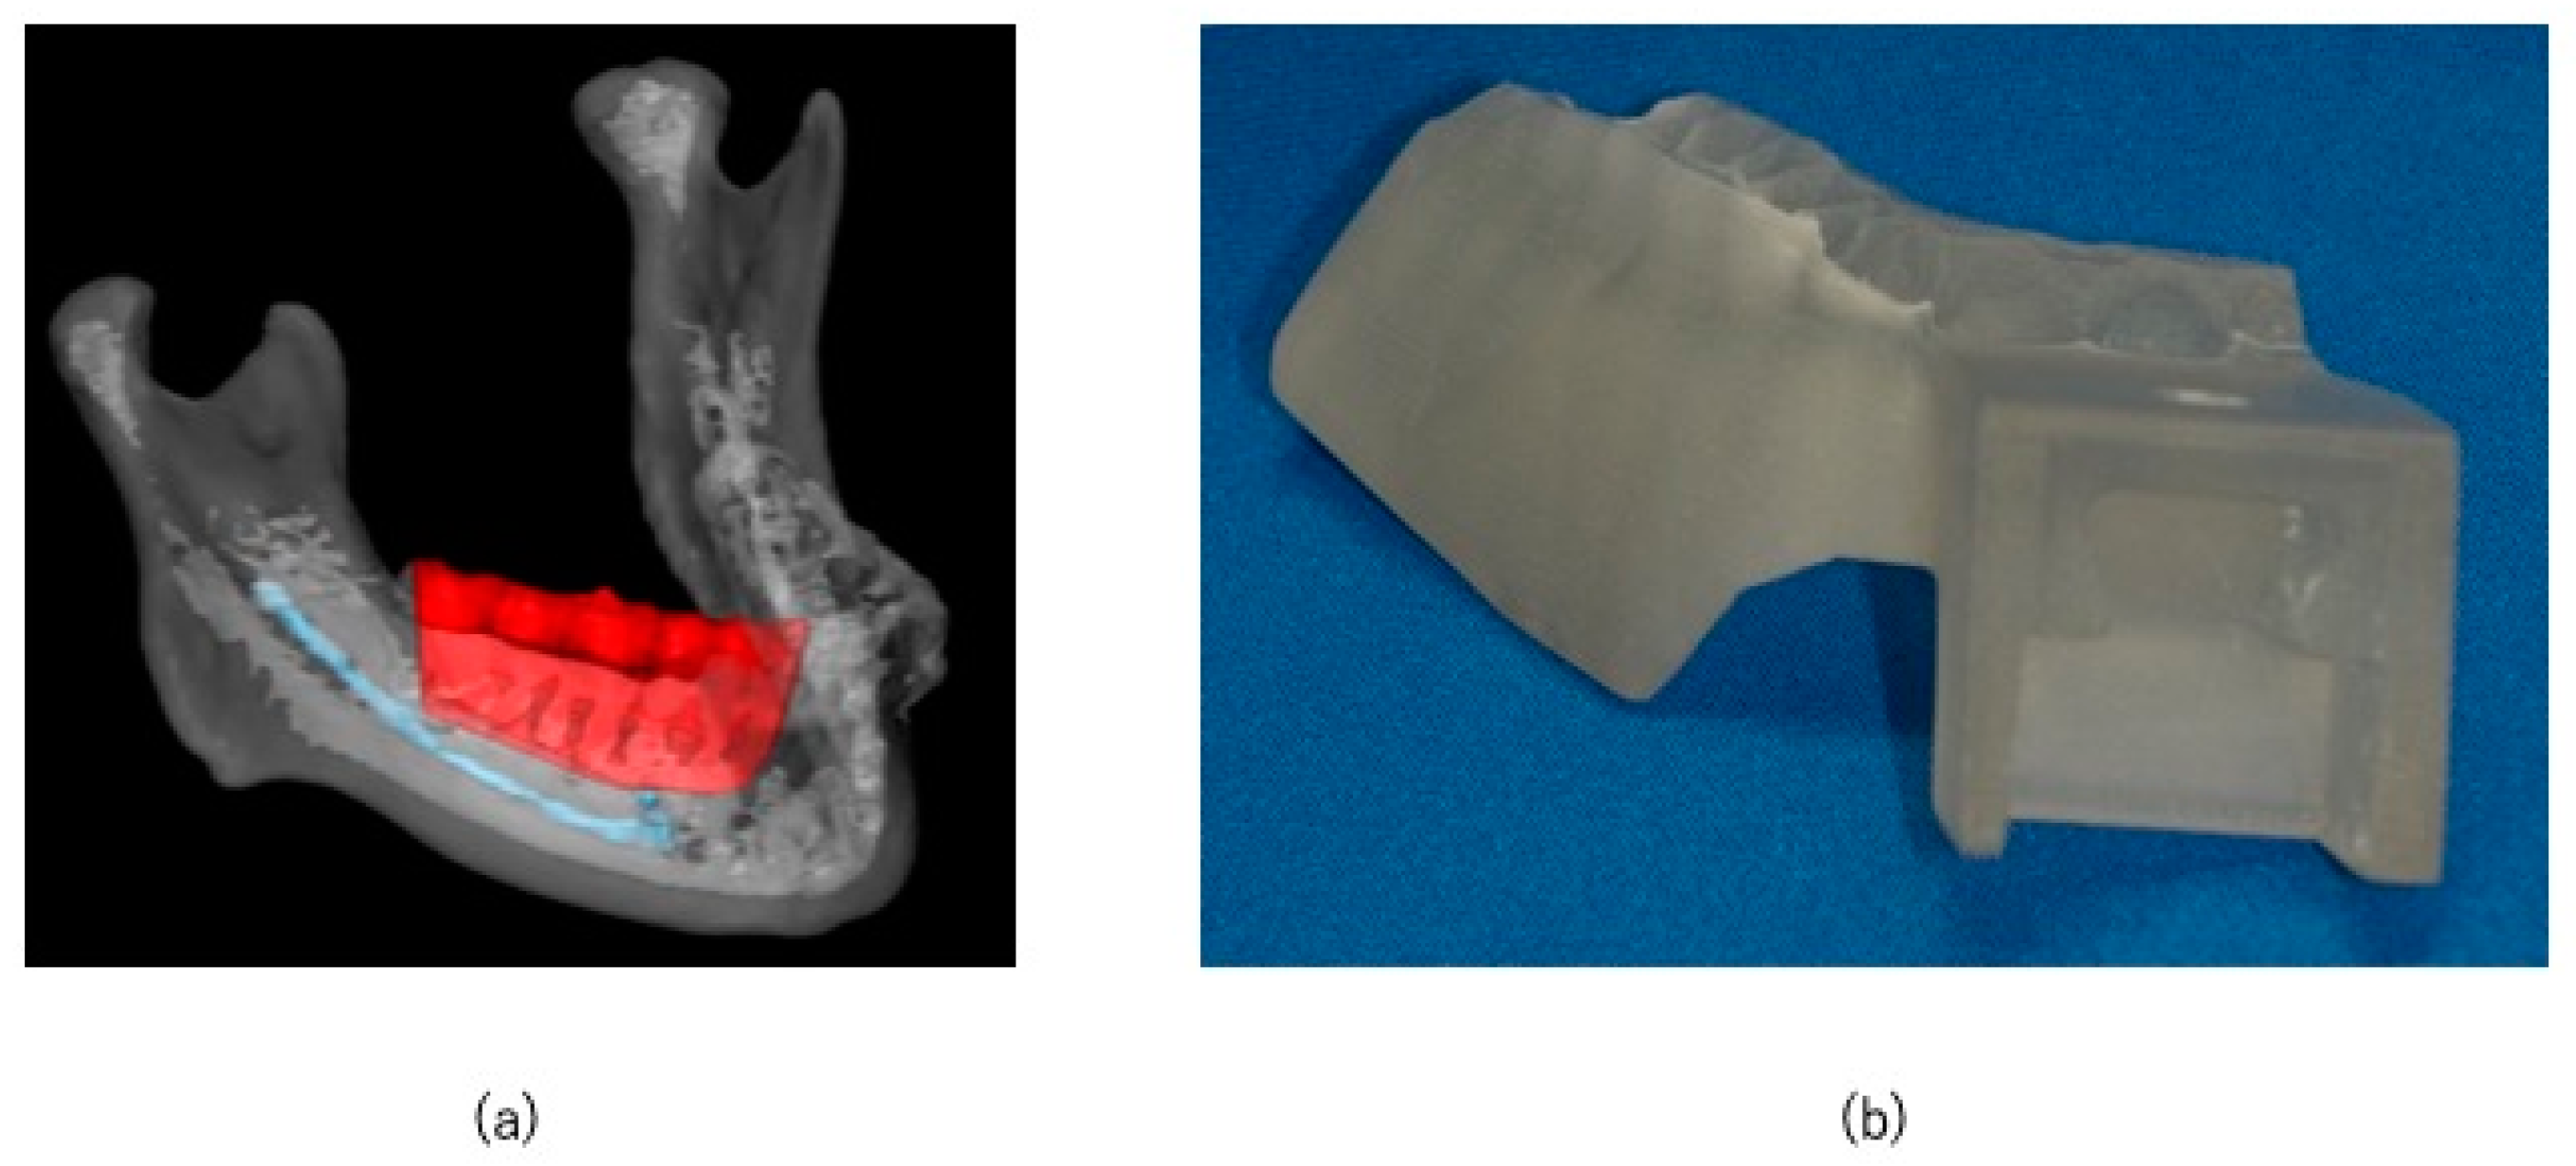

2.2. Preoperative Preparation (CAD/CAM Osteotomy Guide, Virtual Surgery, and Fabrication of XR Application and Registration Marker)